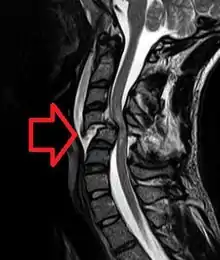

MRI of a fractured and dislocated cervical vertebra (C4) in the neck that is compressing the spinal cord